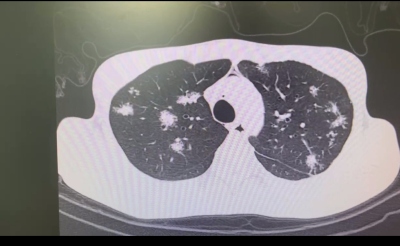

再看看惡性肺結節,這可就像是那些有背景的大妖怪了,可能存在遺傳傾向。

有些人天生就攜帶一些像“BRCA1和BRCA2”這樣的“神秘法寶”(易感基因),這就增加了他們患上肺部結節的風險。就像有些家族性肺癌患者,他們就像是妖怪家族里有特殊本領的成員,攜帶的基因突變會提高患上肺癌(包括肺部結節)的風險。

部分惡性肺結節(如早期肺癌表現)可能和遺傳因素有關。

某些家族中存在特定的基因突變(如EGFR、BRCA等基因異常),就像是妖怪家族有獨特的“魔力傳承”,這些基因變異增加了患肺癌的風險,讓肺部較早出現結節。不過,這可不是直接遺傳肺結節本身,而是遺傳了對肺癌的易感性,使得家族成員在相同環境因素作用下,患肺結節及肺癌的概率相對較高,就像妖怪家族的后代更容易走上“作惡”之路。